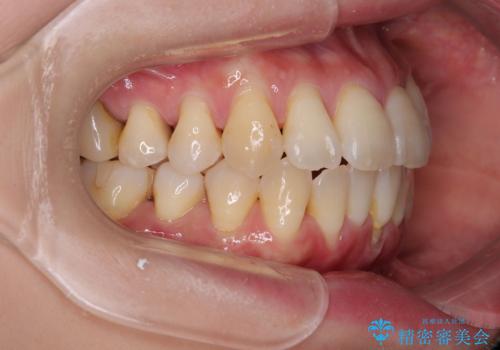

元々の叢生と歯肉退縮傾向になる歯肉であったため、ブラックトライアングルが目立つことが想定されました。

治療過程でブラックトライアングル改善のため、IPR(歯と歯の間を削る)を活用しました。